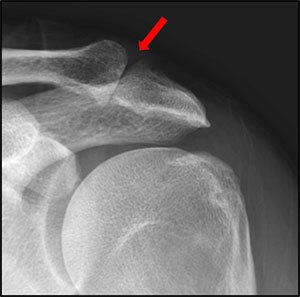

X ray showing AC joint arthritis

- X-rays : X-ray images are often the initial imaging modality used to assess the AC joint. They can reveal structural abnormalities, such as joint space narrowing, bone spurs (osteophytes), or irregularities in the clavicle and acromion.